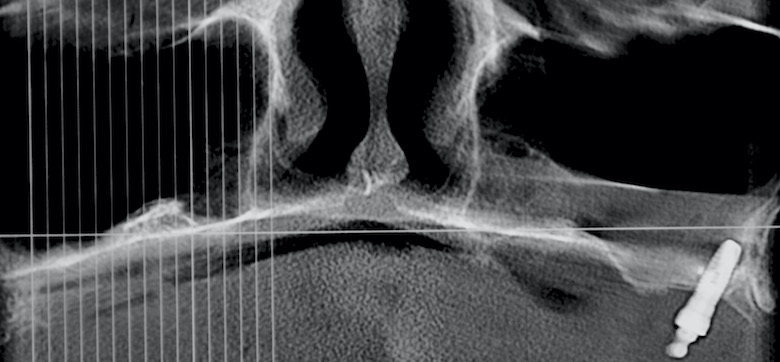

La implantología impulsó una mejora en la calidad de vida de los pacientes, mejorando notablemente no solo su confort y estética sino también su autoestima. Aunque pareciera poco y no lo es, evitó dañar más piezas dentarias para lograr un mismo resultado. Si todo ello es cierto, válido y genuino, el anclaje extramaxilar vino más aún, hace ya tiempo, a dar otro gran salto en la resolución quirúrgico protésica en un sesgo de pacientes que seguían excluidos de los beneficios de la implantología por razones obvias: carecían de stock óseo donde implantar.